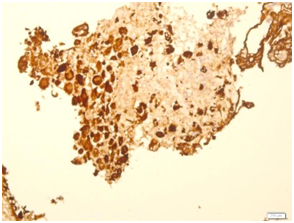

A specimen labeled as left frontoparietal hematoma - ? cavernoma from a 41 year old non-hypertensive female patient on ventilator was received for histopathologic examination. The patient was transferred from outside hospital to neurosurgical department of our hospital for craniotomy and evacuation of intracerebral hematoma. The clinoradiologic diagnosis was spontaneous intracerebral hematoma with intraventricular extension with normal ventricle, probably due to cavernoma. The microscopic examination of the specimen revealed extensive hemorrhage with peripherally placed mono-nucleated and multinucleated atypical cells. The mononucleotide cells were medium to large size with abundant cytoplasm and central large hyperchromatic nuclei. The multinucleated cells were large with abundant eosinophilic cytoplasm and hyperchromatic multinucleated bizarre nuclei. They were considered as cytotrophoblasts and syncytiotrophoblasts respectively (Figure 1-4). Immunohistochemistry showed that the atypical cells were CKAE1AE3 +, HCG+, GFAP-, CD31- and Vimentin- (Figure 5 to 10). A thin rim of GFAP positive glial tissue was seen in one fragment. Based on these findings, a diagnosis of metastatic choriocarcinoma was made. The patient survived the surgery and started recovering neurologically, but chose to go back to her own country for further management. So, we could not get any details of her obstetric history or previous medical illness.

Figure 7 HCG.

Figure 8 HCG

Surgically resected blood clots from intracerebral hemorrhage (ICH) for histopathological examination are the frequent samples from neurosurgical department. Intracerebral hemorrhage has a number of causes, including: hypertension, head trauma, arteriovenous malformation, cavernoma, ruptured cerebral aneurysm, primary or metastatic neoplasm, bleeding disorder and medication. Incidence of bleeding is more in metastatic tumor than primary tumor.1 Most common metastatic tumors known to cause intracerebral hemorrhage are choriocarcinoma, bronchial carcinoma, melanoma and renal cell carcinoma. In our case, on H&E examination, histopathologic differentials were metastatic choriocarcinoma, metastatic sarcoma and symplastic cavernoma/hemangioma. Cytokeratin positivity and negative vimentin ruled out possibility of sarcoma, negative CD31 ruled out hemangioma and positive HCG (with positive cytokeratin) confirmed metastatic choriocarcinoma.4 Serum/CSF beta-HCG ratio will be decreased in metastatic intracerebral choriocarcinoma,5 In this case, Serum/CSF beta-HCG ratio and other investigations could not be done as it was an unsuspected case transferred from outside hospital in critical condition and the patient went back to her own country for further management. The choriocarcinoma is a rare highly malignant vascular trophoblastic tumor with high incidence of metastasis. The most common sites for metastatic choriocarcinoma are lung, brain and liver. Rarely, it can metastasize to gastrointestinal tract, kidney, spleen, genital tract and lymph nodes.